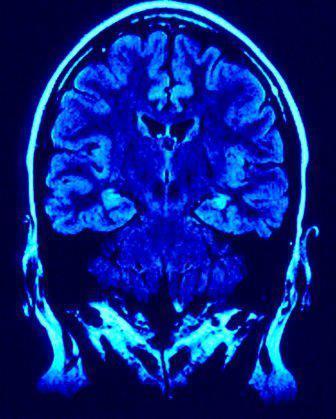

"Injury Compensation Fund - The fund of at least $675 million will be available to pay monetary awards to retired players who present medical evidence of severe cognitive impairment, dementia, Alzheimer's, ALS, or to their families. The precise amount of compensation will be based upon the specific diagnosis, as well as other factors including age, number of seasons played in the NFL, and other relevant medical conditions. These determinations will be made by independent doctors working with settlement administrators appointed by the District Court."

As a result, in order for an injured player or his family to obtain money from this fund, determinations as to the "severity" of the brain injuries will have to be evaluated by "independent doctors working with settlement administrators appointed by the District Court." Of course, this begs the question, what about the players who are only determined to have mild traumatic brain injuries? Where is the line going to be drawn determining the degree of injury for these players?